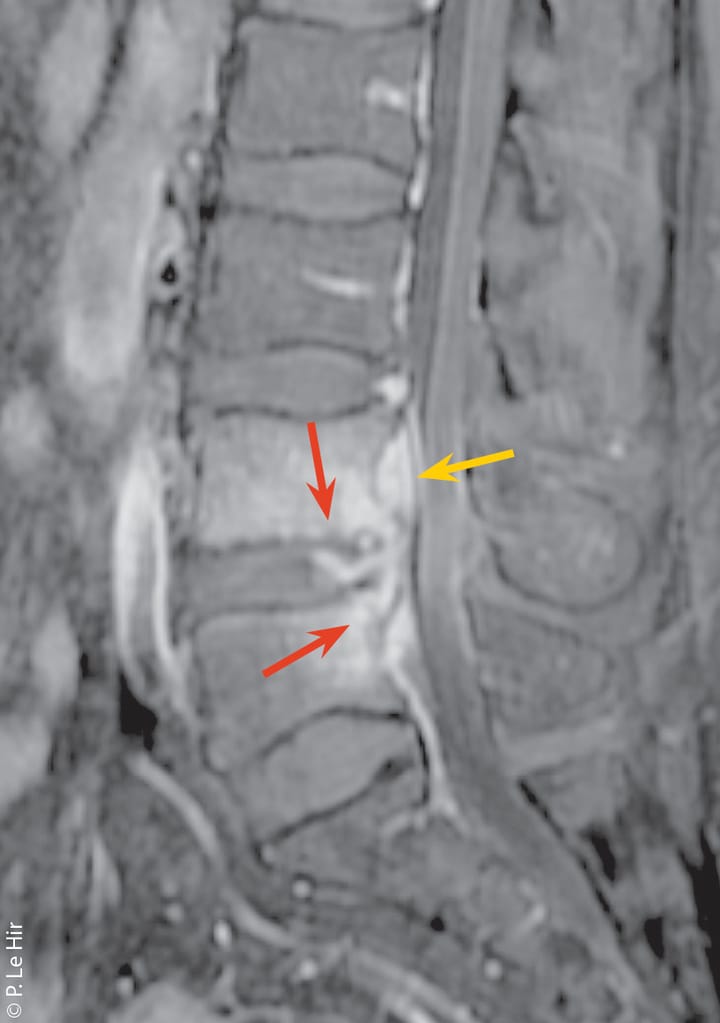

Neurologie Neurostimulations manuelles et lombosciatique : apport de la Posturothérapie NeuroSensorielle (PNS)